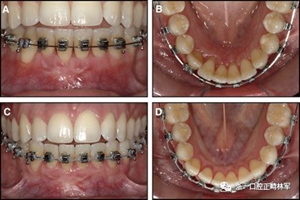

粘合保持器被移除,并放置固定裝置(圖15),僅限于患者要求的下頜弓。在第一階段牙周過程中,將結(jié)締組織移植物置于下頜右側(cè)中切牙的面?zhèn)取?個(gè)月后進(jìn)行第二階段牙周過程(圖16)。包括有意識的垂直骨質(zhì)評分以啟動區(qū)域加速現(xiàn)象,以及顯著的面?zhèn)群蜕鄠?cè)植骨以糾正骨開窗。隨著時(shí)間的推移,全維度弓絲及其表達(dá)的牙齒間扭矩差異顯著改善(圖17)。明智的鄰間減少之后,間隙關(guān)閉擴(kuò)大接觸面,消除不美觀的黑三角。在脫粘之前也校正了牙齒排列和牙弓形態(tài)(圖18)。之前和之后的三維圖像(圖19)突出顯示在下頜右側(cè)尖牙面?zhèn)缺砻嫔瞎堑脑黾右约扒把姥栏恢玫母纳啤S捎谙骂M切牙的伸長被認(rèn)為是不嚴(yán)謹(jǐn)?shù)?,因此輕度前牙開合沒有被矯正。

圖17.治療進(jìn)展:A和B,二次手術(shù)后愈合; C和D,幾個(gè)月后牙根扭矩的改善。

圖18.脫粘后的最終圖像:A,正面視圖; B,咬合面視圖。 進(jìn)一步的牙齒移動以糾正輕度前牙開合被認(rèn)為不符合患者的最佳利益。